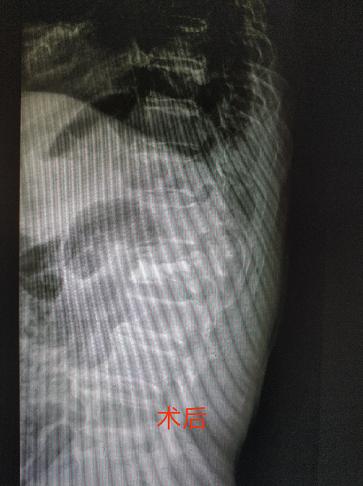

患者为一84岁男性,曾上朝鲜战场抗美援朝。就医前两周因坐车颠簸而致腰部疼痛,不能下地行走,自行卧床休息后疼痛无明显缓解,影响饮食和睡眠,至本院门诊就诊,查DR和CT确诊为腰1椎体压缩性骨折,收住院治疗。副院长、骨科主任医师朱兴元诊疗小组接收患者后,组织全科讨论,为患者制定了详细的手术计划。7月16日,在麻醉科监护下手术团队为患者施行了经皮单侧椎弓根穿刺全椎体成形术。手术仅耗时不到一小时便取得圆满成功,术后两小时患者即可下地自主行走,术前疼痛症状完全消除,两日后康复出院。